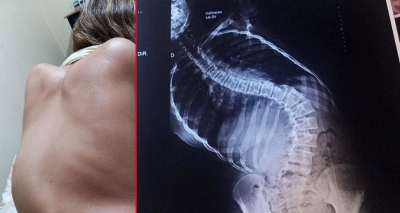

Mariliense vende bolos para conseguir pagar cirurgia de R$ 150 mil da filha